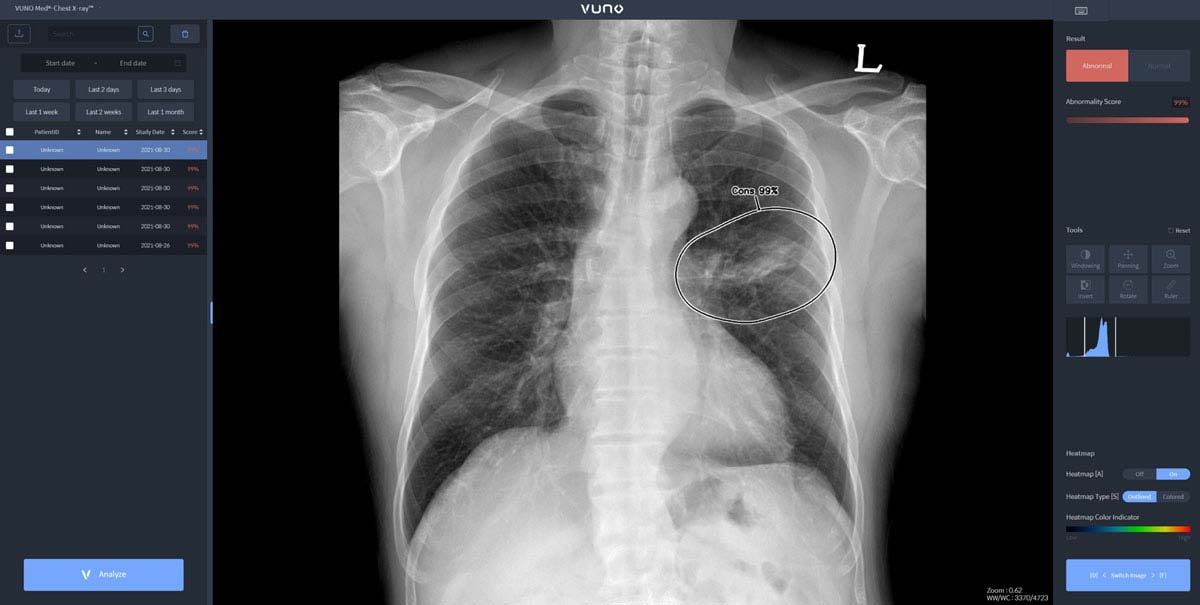

자이드 군 병원에 도입된 솔루션은 이동형 엑스레이 장비에 뷰노의 AI 기반 흉부 엑스레이 판독 보조 솔루션 '뷰노메드 체스트 엑스레이(VUNO Med®-Chest X-ray™)'를 탑재한 패키지 제품이다. 별도의 차폐 시설 없이 다양한 상황에서도 쉽게 환자의 흉부 엑스레이 촬영을 할 수 있는 이동형 장비에 인공지능을 연동해 수 초 이내에 판독 결과를 확인할 수 있다.

한편, 뷰노메드 체스트 엑스레이는 흉부 엑스레이 영상에서 결절, 경화, 간질성 음영, 흉수, 기흉 등 주요 이상소견을 높은 정확도로 탐지하는 인공지능 솔루션이다. 의료진에게 이상소견의 소견명과 위치를 제시해 결핵, 폐렴 등 주요 폐 질환 진단을 돕는다. 경량화된 모델로 개발돼 다양한 엑스레이 장비에 쉽게 연동할 수 있는 것이 특징이다.